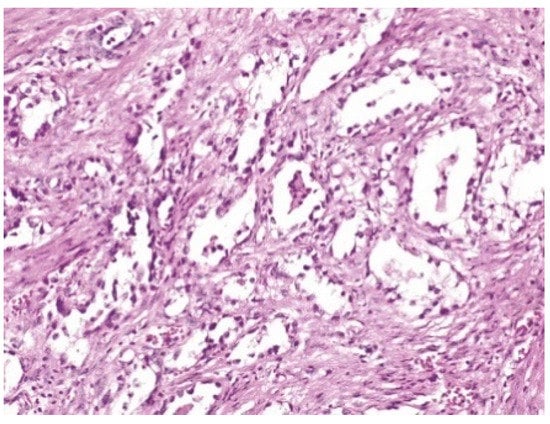

| LEEP | atypical mesonephric hyperplasia with a malignant transformation zone—mesonephric adeno-carcinoma with moderate cell pleomorphism, moderate mitotic activity, without invasion of the lymphovascular space, resection limits tangential to the lesion |

| Radical vaginal trachelectomy with laparoscopic pelvic lymphadenectomy | Uterine isthmus—endocervix—upper limit of resection with benign mesonephric hyperplasia with areas of atypical mesonephric hyperplasia, showing moderate atypia; |

| Cervix with previous conization –appearance of atypical mesonephric hyperplasia; zone of stromal invasion and malignant transformation—endocervical mesonephric adenocarcinoma with moderate cell pleomorphism and mitotic activity, intraluminal detritus, added inflammation | |